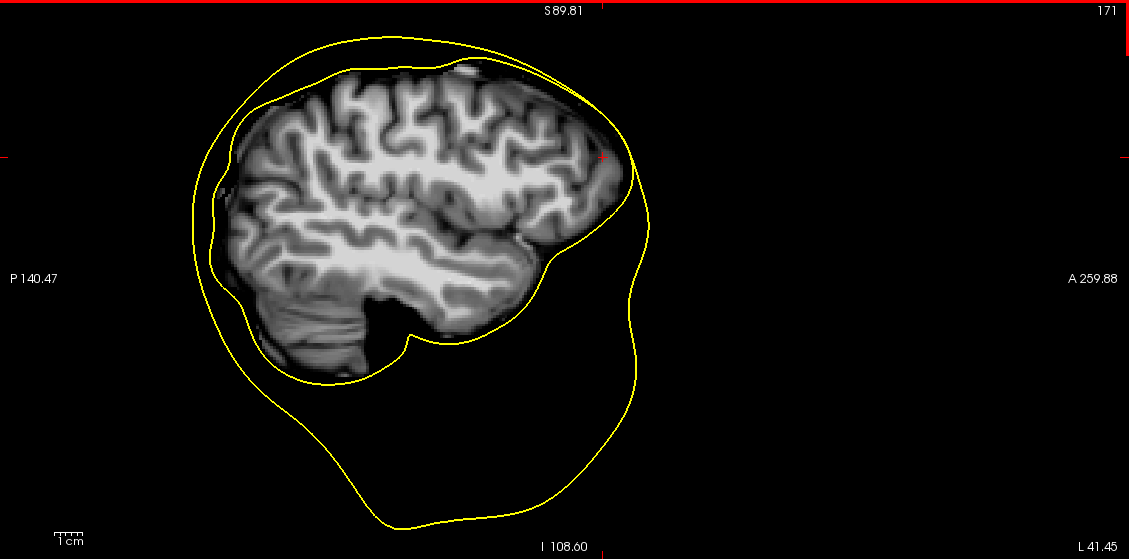

For a lot of subject, the process fails because the brain extraction step of the mri_watershed algorithm does not properly segment the brain and often keeps part of the dura matter. As a results, the expanded brain surface (i.e inner skull) is often not completely inside the outer skull area.

mri_watershed brain mask